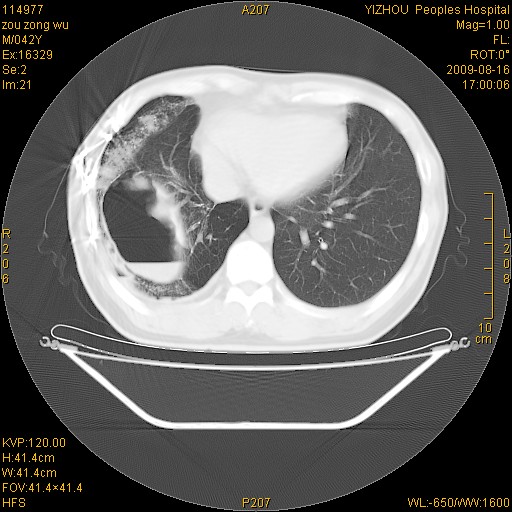

以下是引用zjzjr在2009-8-17 10:42:00的发言:[br]右侧间质性肺炎伴纤维化,右肺下叶肺囊肿伴感染(不除外外伤后引起),右肺野及胸壁软组织\\肝内见多发斑点状,中枪了吧.右侧胸膜肥厚\\粘连.